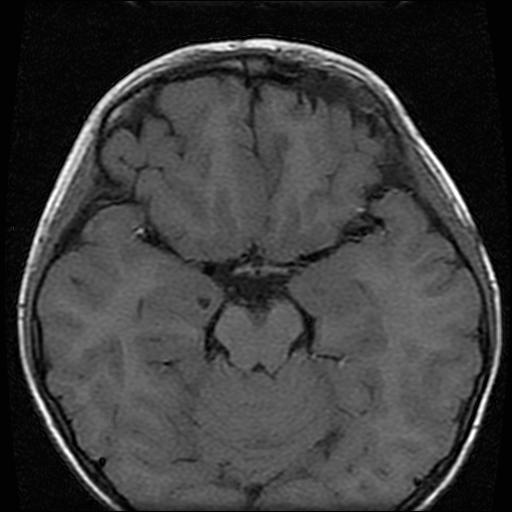

6岁小儿,左侧视神经瘤术后。现左侧视力减退。